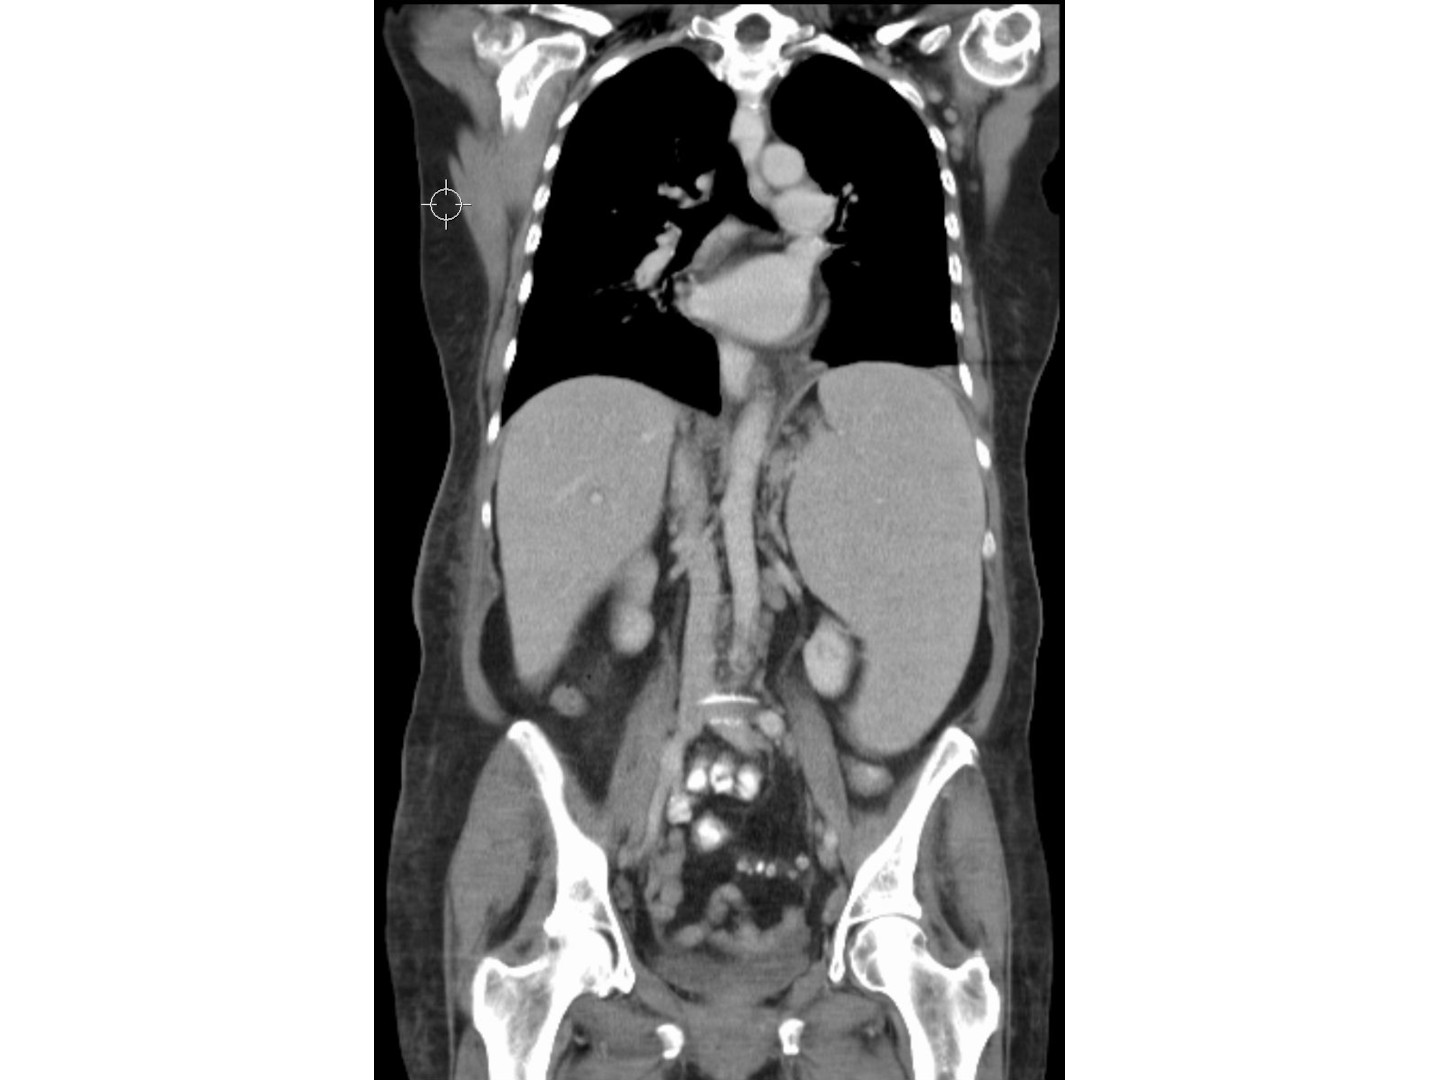

Diagnostik > Apparative Diagnostik

Leberbiopsie: läppchenzentrale Nekrose

Biopsienadel: durch Ohrläppchen (zentral) und schwarze Rose

Die massive Einwanderung von neoplastischen Lymphozyten in die Leber hinterlässt Spuren: In der Leberbiopsie findet man eine läppchenzentrale Nekrose.